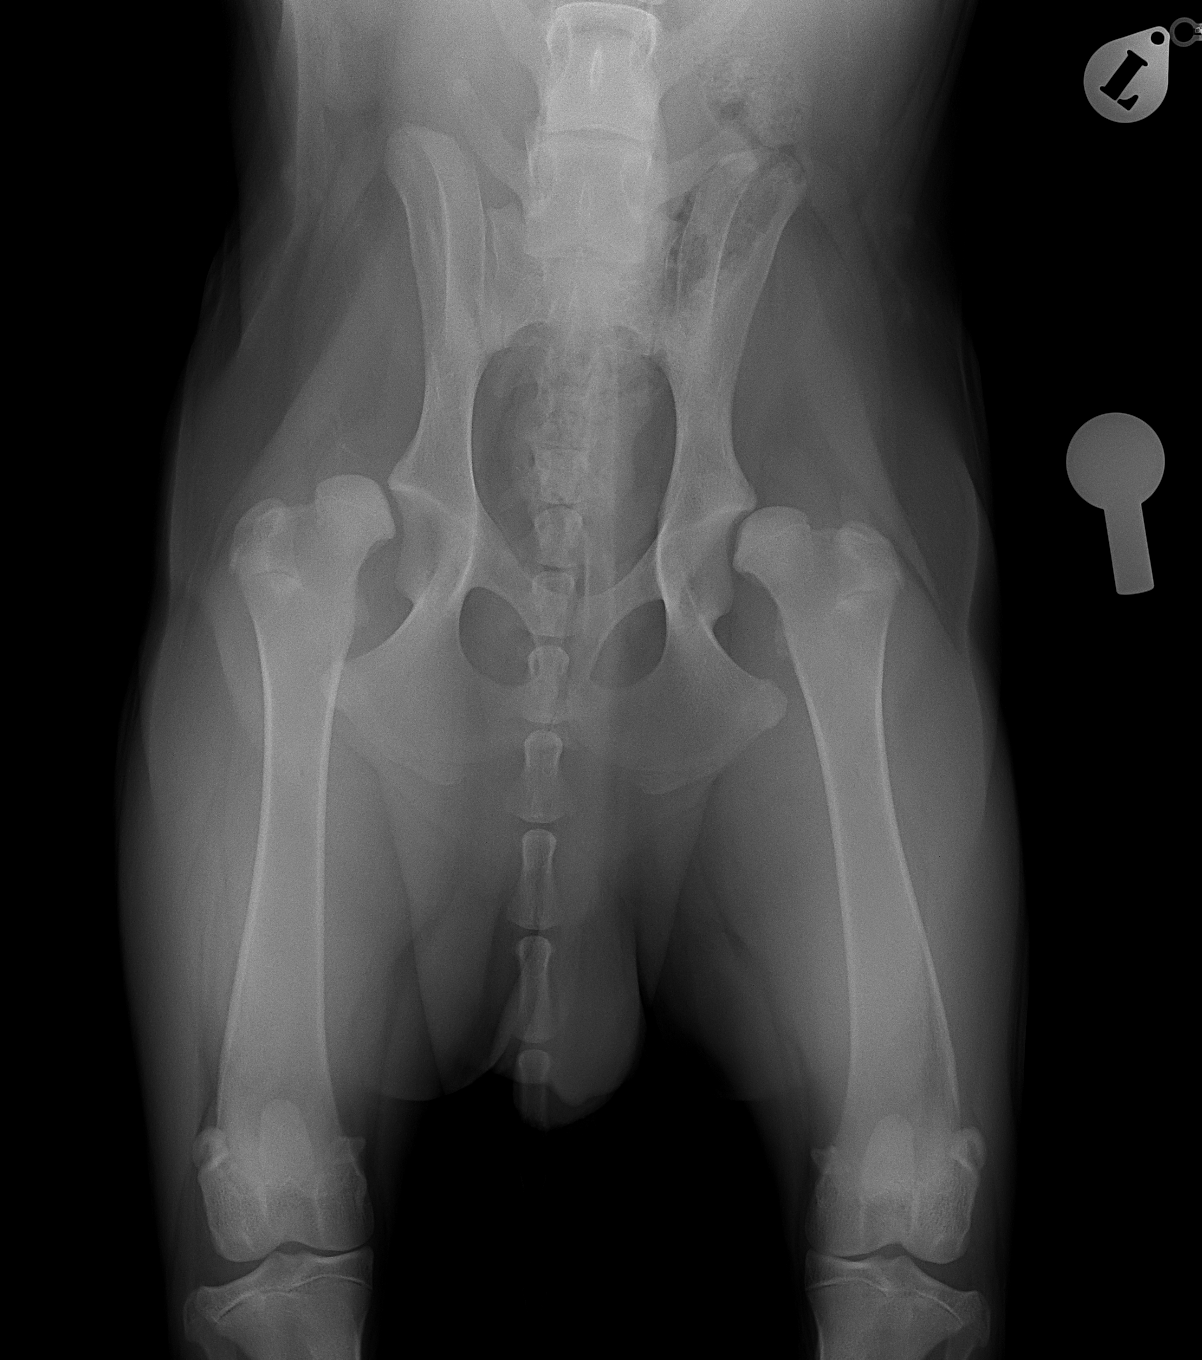

THR #24 大型犬の股関節形成不全のパピーに最も除痛効果と機能回復が期待できるトータル・ヒップ・リプレイスメントで対応しました。しばらくは安静が必要です。 症例カテゴリー 放射線治療整形外科軟部組織外科脳神経外科内科腫瘍外科救急・集中治療リハビリテーション科腫瘍内科内視鏡科脳神経科呼吸器外科中医・漢方猫の腎移植循環器科